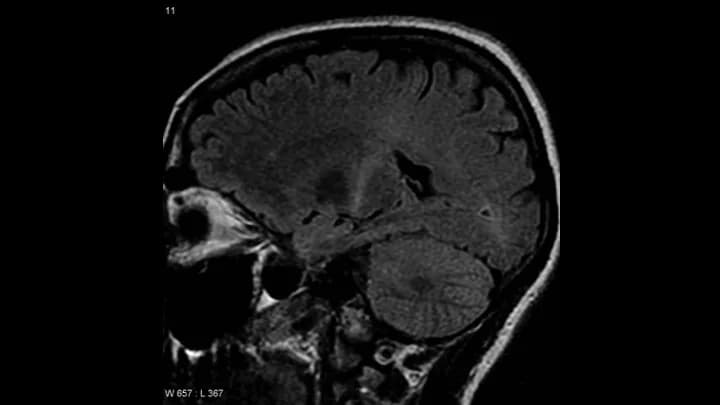

• Cervical spine CT or MRI scans to ensure that there is no disease or injury to the neck

• Head CT or MRI of the brain to rule out other conditions